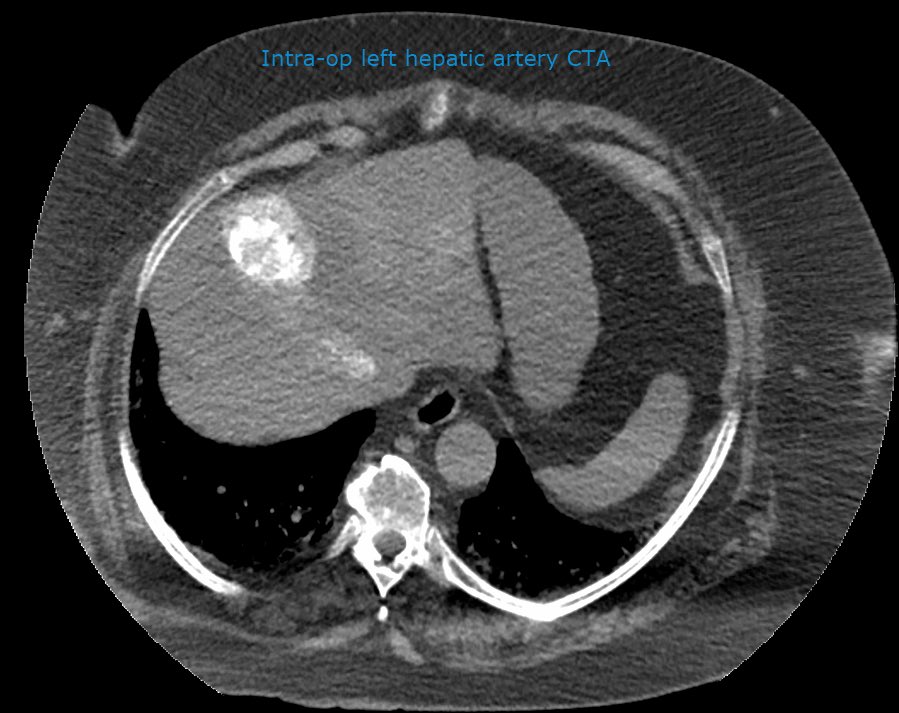

should be an AWESOME outcome #irad

Patient with seg4 HCC and celiac axis atherosclerotic occlusion (and aortioiliac disease). Difficult navigation via SMA collateral to GDA and finally seg4 branch of LHA #Y90. Hoping for a great outcome @MoffittNews @NaineshParikhMD Intra-op CTA @SiemensUSA Maestro @MeritMedical